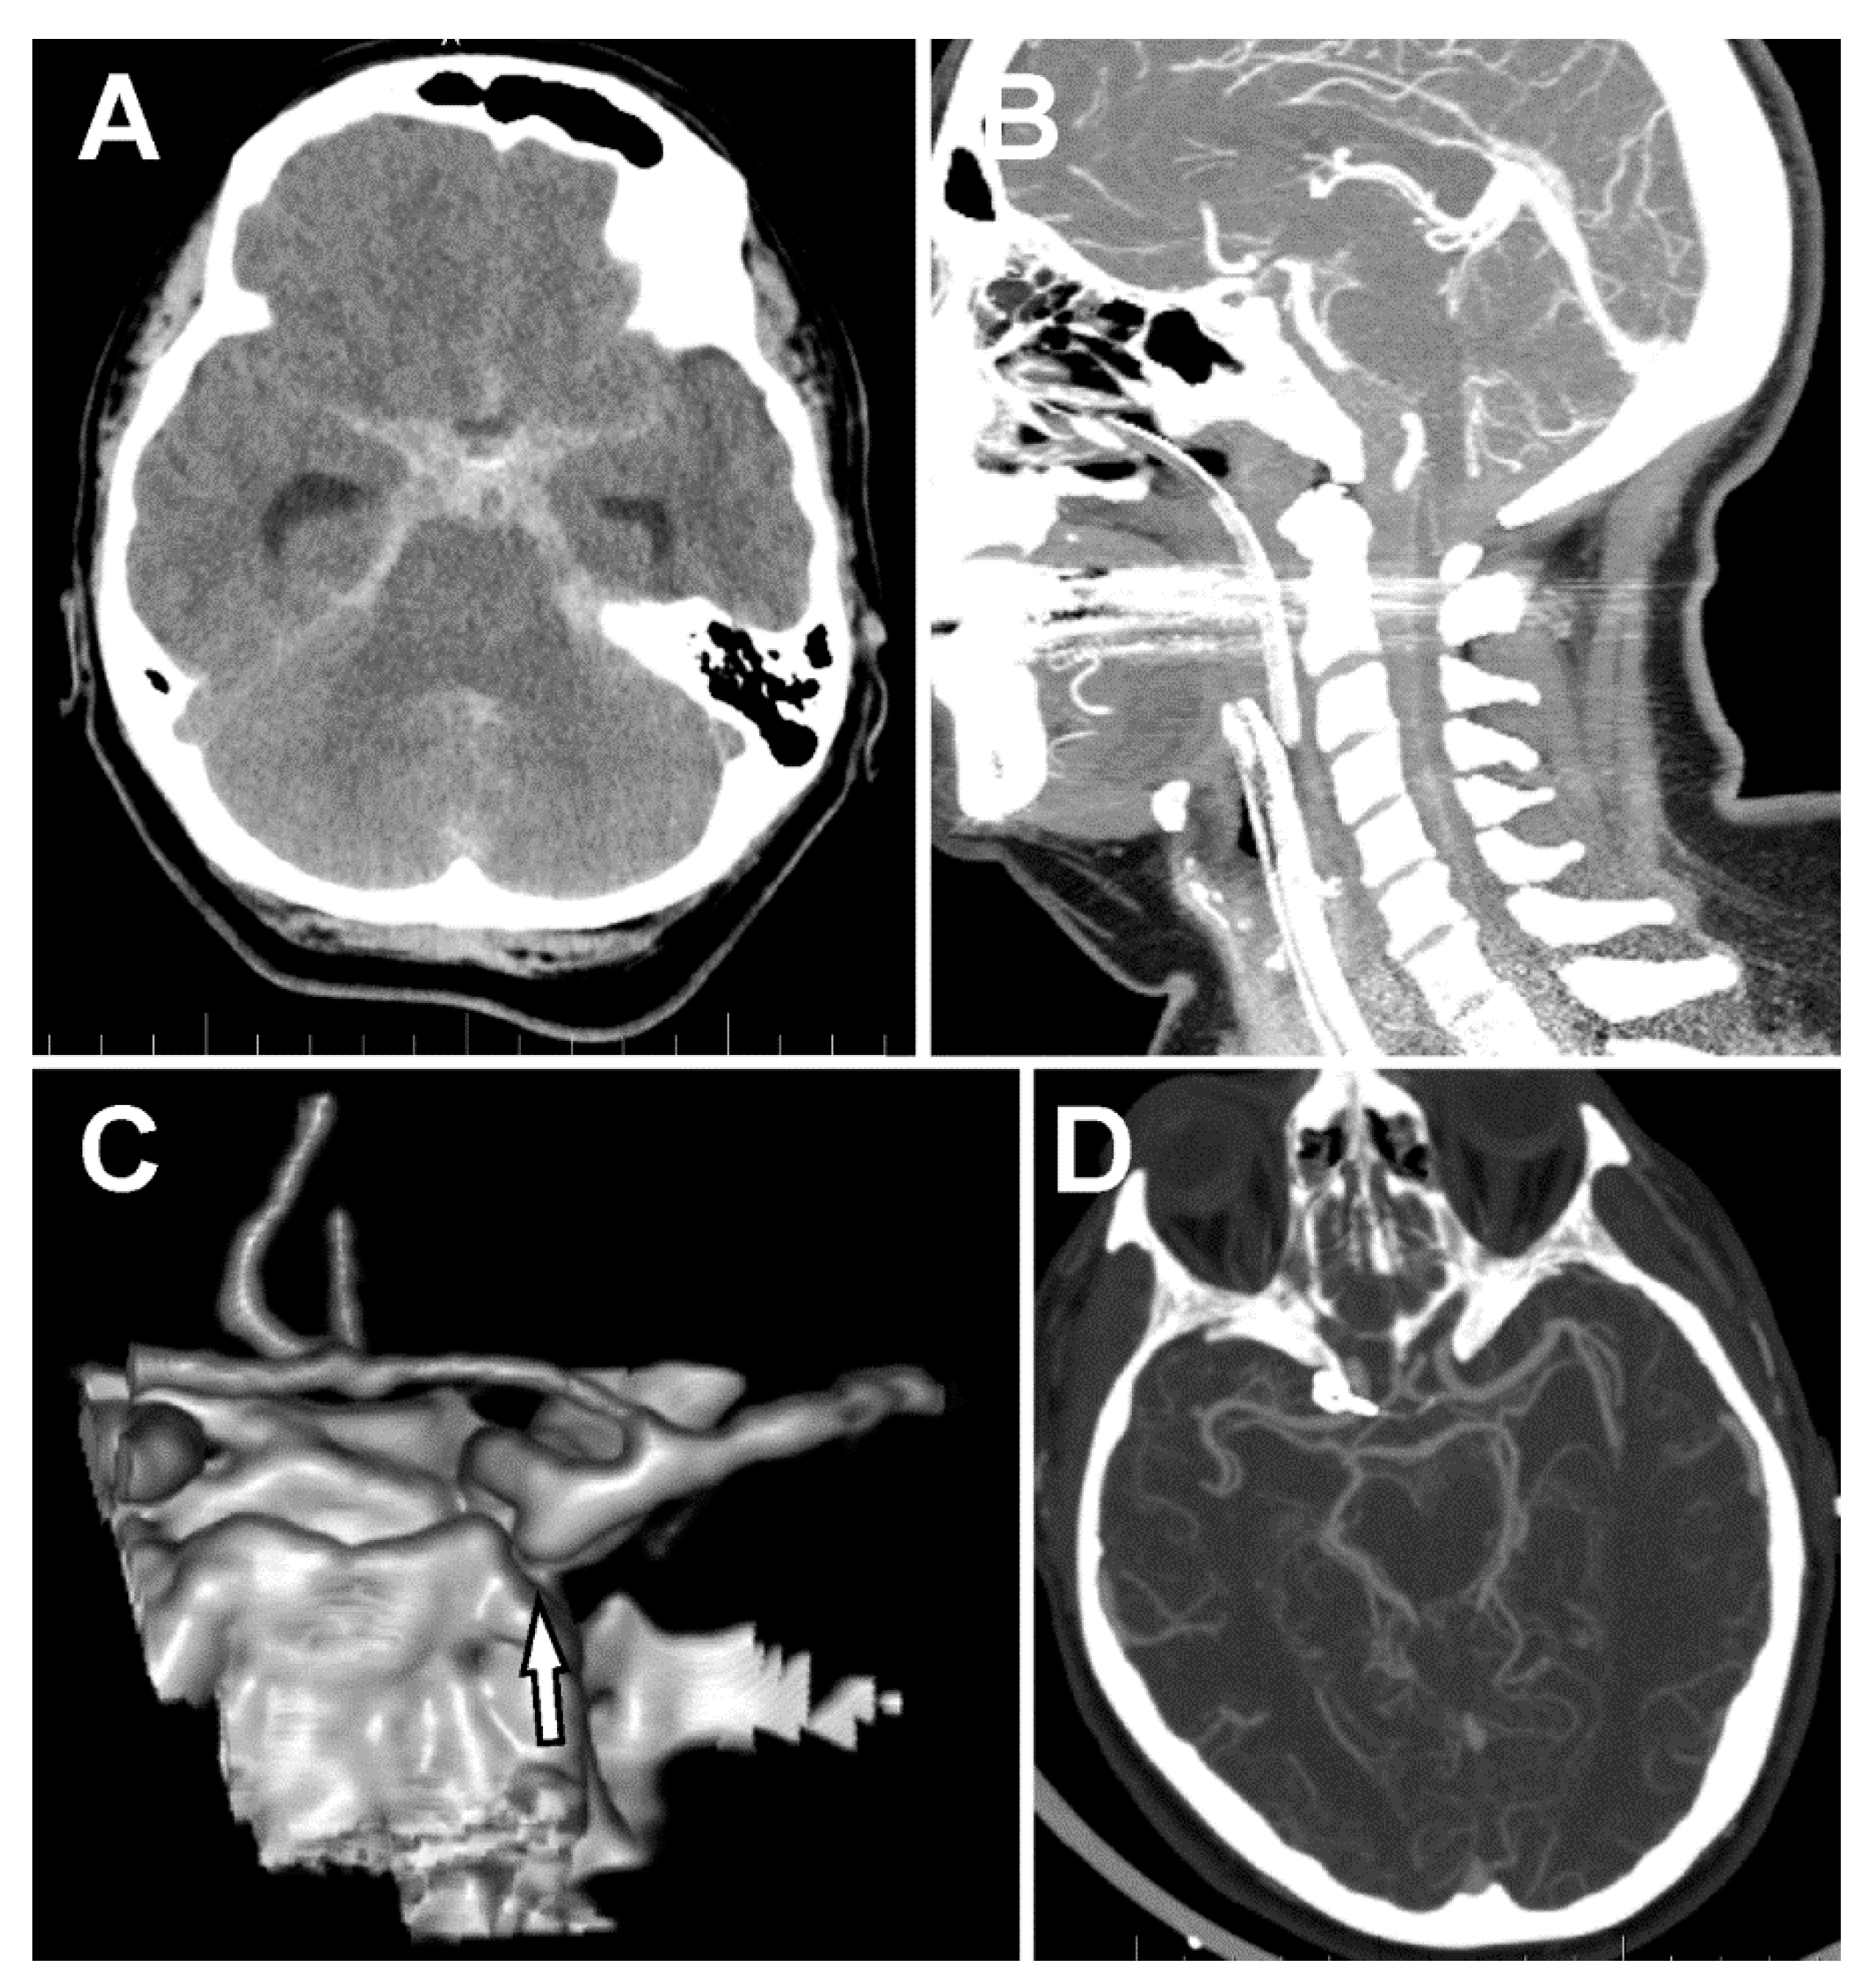

Spontaneous Subarachnoid Hemorrhage in a Patient with a Co-Existent Posterior Communicating Artery Aneurysm and Cervical Spine Aneurysm Associated with Ventral Arterio-Venous Fistula

2. Case Report